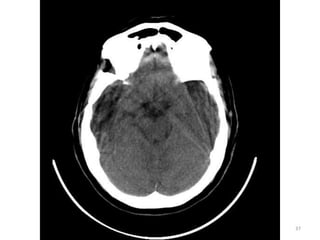

1. HEMISFÉRIO OCCIPTAL D

2. LOBO TEMPORAL D

3. NERVO ÓPTICO E

4. CÉLULAS MASTÓIDEAS E

5. SEIO FRONTAL

1

2

3

4

5

88